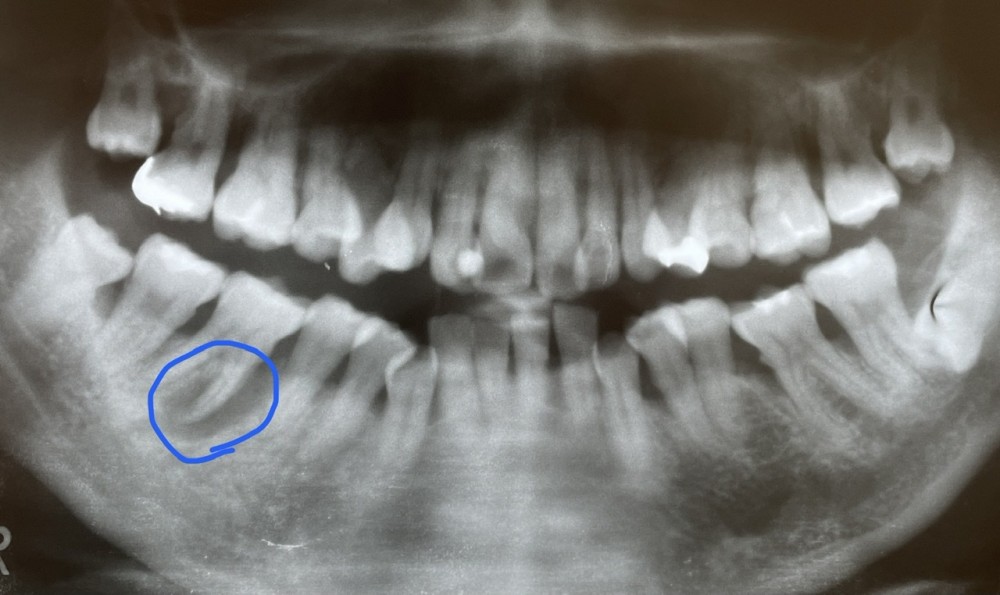

下のエックス線写真は、初診時のものです。右下奥歯の歯茎の激しい腫れと痛みを訴え、救急相談ダイヤルから当院を紹介された患者さまです。

青い線で囲んだ部分に、歯周病による歯槽骨の吸収が起きています。

上行性歯髄炎という激しい痛みを伴う状態でした。

通常であれば抜歯か、もしくは歯根分割して近心根を部分抜歯し、その後にブリッジを行うのが妥当とされる状態です。